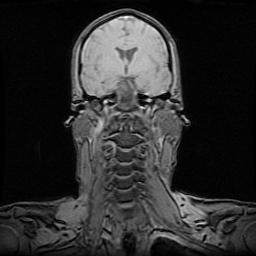

MRI of my brain after the stroke. Vertebrae coming up from bottom. Lateral ventricle is dark in middle, with cortex wrapped above, and brainstem below. The clot and affected area are too small to see. There was swelling in an area about the size of a finger tip in the pons. Part of the corticospinal nerve which controls the left side of my body was killed, and part of it was damaged and probably recovered. My left side may also have recovered by recruiting the ten percent of the corticospinal tract which does not cross over. Or something else.

This page shows MRI images, and my daily blog as I experienced the stroke and then used every bit of my neuroscience training to augment the wonderful physical therapy at Fanny Allen hospital. I recovered most of my basic motor functioning.